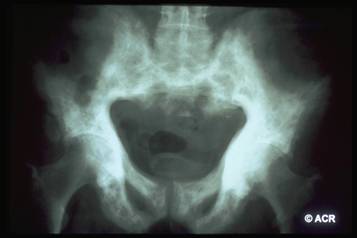

Osteoporosi

Sindrome caratterizzata dalla diminuzione della massa ossea con conseguente facilità alle fratture

Il 30% della massa ossea viene persa prima che l'osteoporosi possa essere evidenziata dalle radiografie;

Evidenzia le fratture.

La riduzione della massa ossea costituisce il principale fattore di rischio per le fratture scheletriche; il suo valore viene espresso come differenza rispetto alla popolazione giovane normale (T-score);

- osteopenia: il T-score è compreso tra -1 e -2,5;

- osteoporosi: il T-score inferiore a -2,5.

Clinica: fratture

Strumentale: densitometria